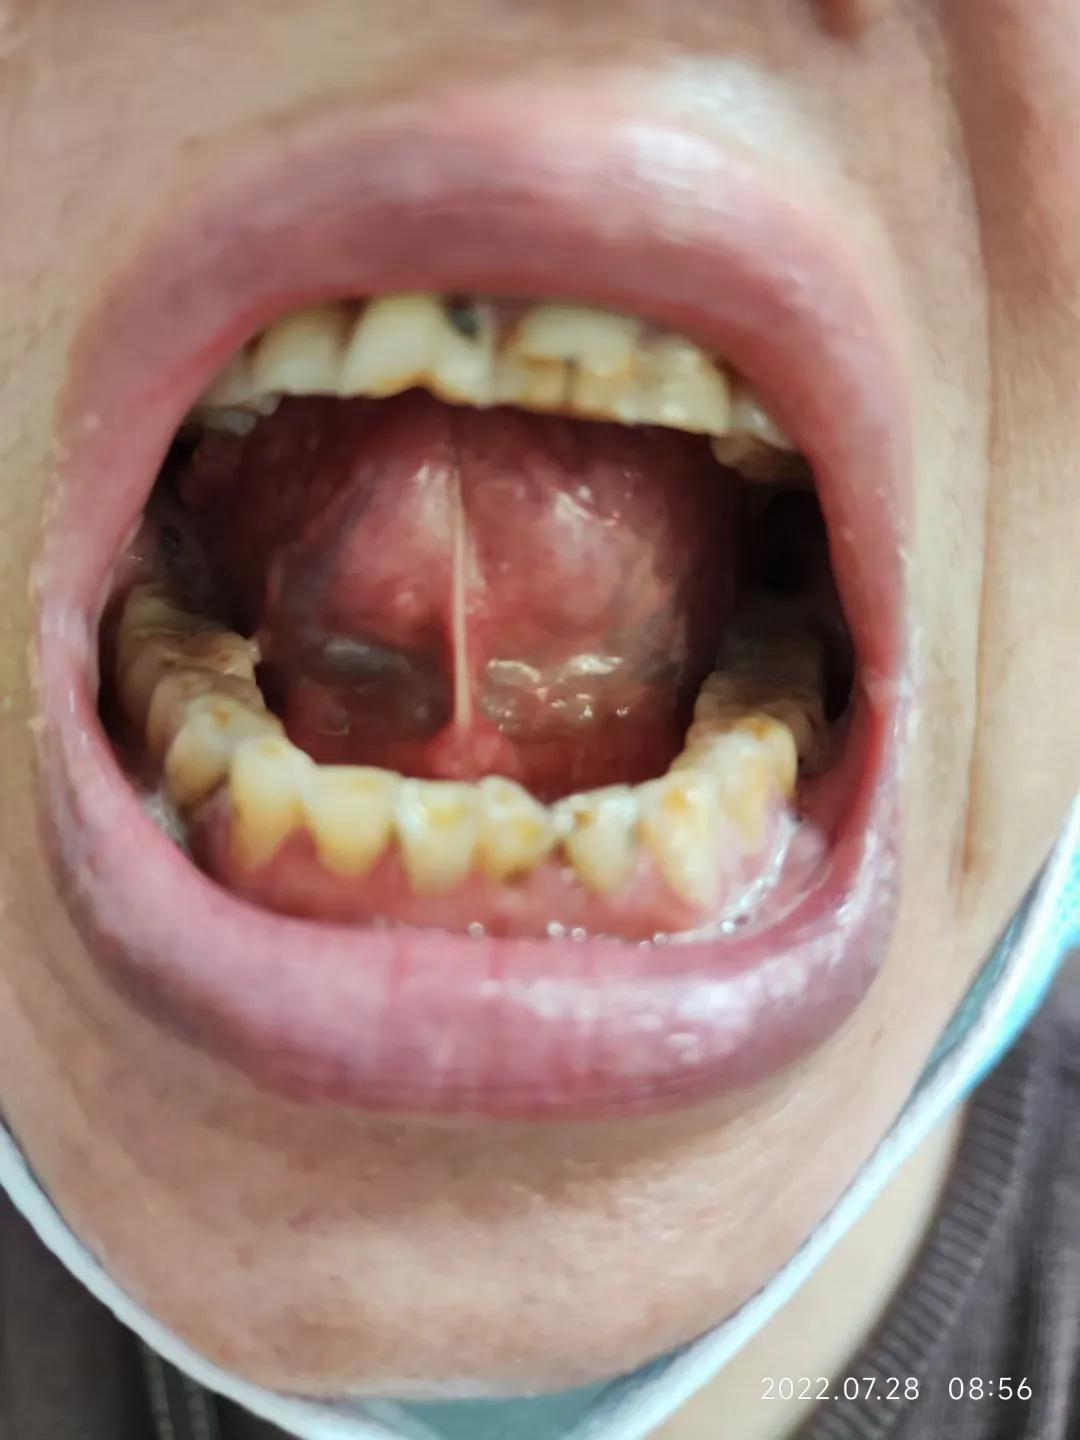

患者,女,60岁,2022.7.28来诊。

患者诉,2018年确诊“干燥综合征”。此后服用常规西药治疗。

2022.7.28来诊